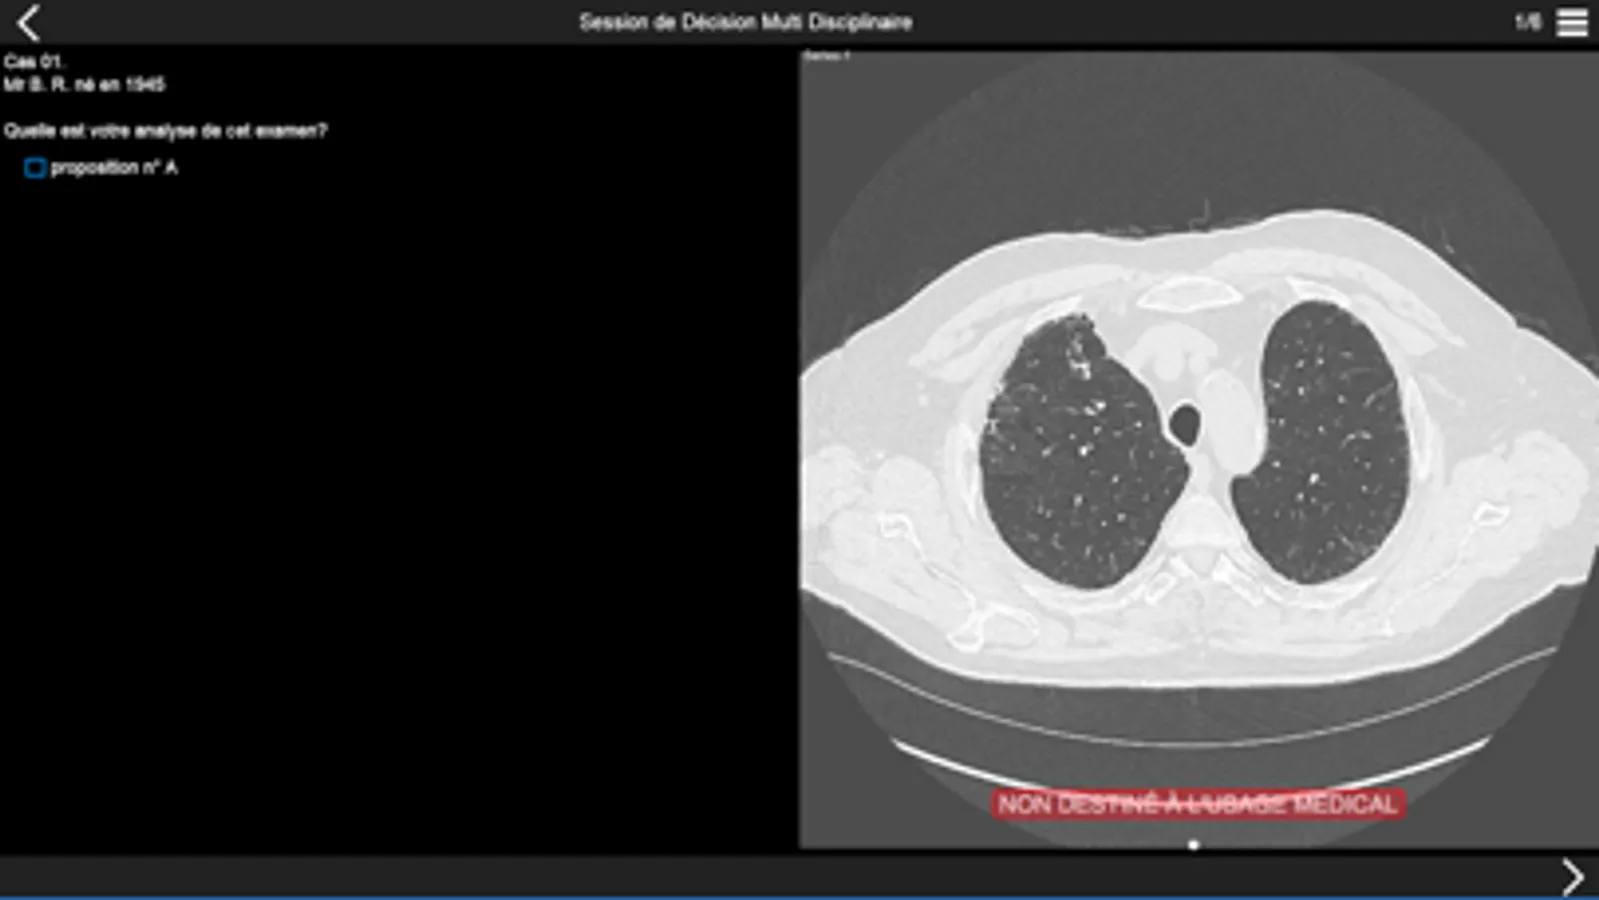

Consultez les examens tomodensitométriques des cas cliniques de pneumopathie infiltrante présentés lors de la session de discussion multidisciplinaire qui aura lieu dans la première partie de l'après-midi.